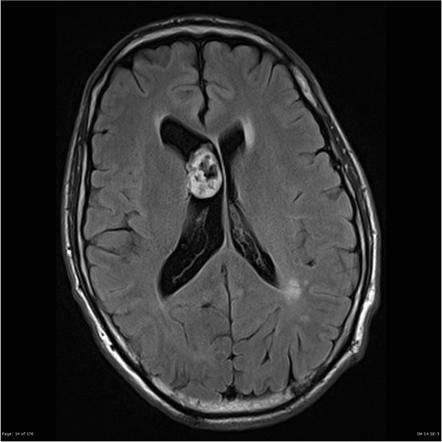

Flowchart of potential head injury rehabilitation services (HI=head injury; rehab=rehabilitation) - Brain Tumors

Brain Tumor

MRI brain tumor.